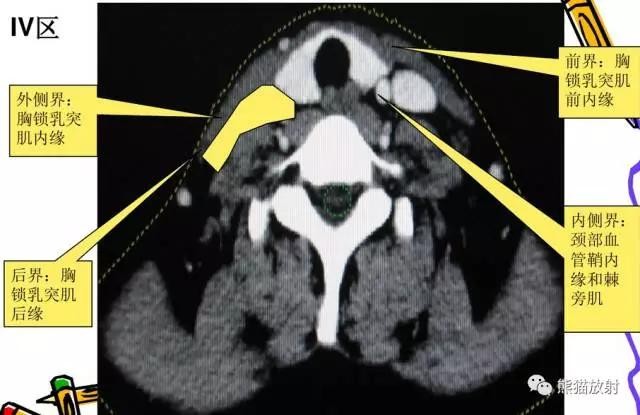

IV区:颈内静脉链下组